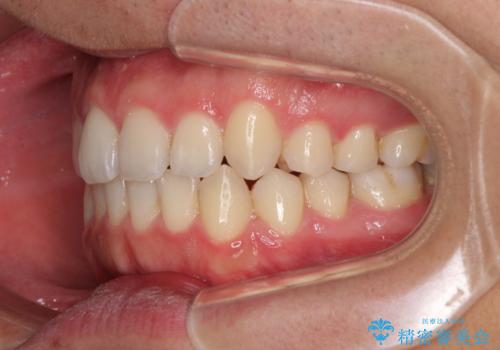

狭い歯列と前歯のデコボコ インビザラインによる矯正治療

- 上下前歯のデコボコを気にして来院された患者様です。

インビザラインによる上下歯列の拡大と、IPR(歯と歯の間を削る)にるスペースの獲得により、前歯のデコボコと狭い歯列を改善することとしました。

比較的軽度な歯列不正であったため、治療期間はそれほど長くはならないと予想されました。

しかしながら、あまりしっかりとマウスピースを装着していなかったため、思いの外期間が長引いてしまいました。

また、仕上がりの歯列にも若干の叢生が残ってしまいました。